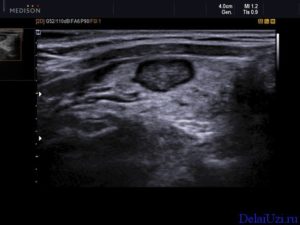

- Неправильный выбор метода УЗИ. Некоторые органы можно осмотреть на УЗИ несколькими способами. Например, рассмотреть женские половые органы женщины можно через брюшную стенку, прямую кишку и половые пути. Однако, пациенток с большим избыточным весом осматривать через переднюю брюшную стенку нецелесообразно, поскольку толстый слой подкожной жировой клетчатки исказит картину. Максимально правильную диагностику в этом случае можно сделать только при трансвагинальном обследовании. Поэтому неправильный подбор методики осмотра приведёт к искажению результатов.